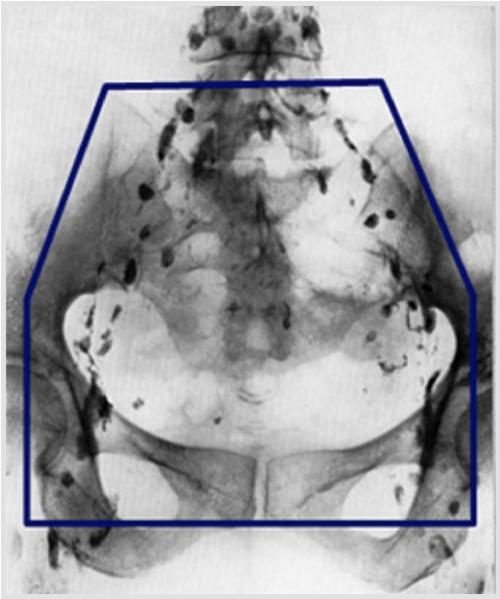

外部照射の治療範囲は、子宮の病巣から腫瘍が拡がる可能性のある腟、子宮傍結合織、骨盤リンパ節までを含めます。図aは、リンパ管造影の写真に照射野を重ねたものです。骨盤リンパ節(内・外・総腸骨・閉鎖節・仙骨前リンパ節)は照射野に含まれます。図bはCT上で再構成した、実際の照射範囲の一例です。

図a